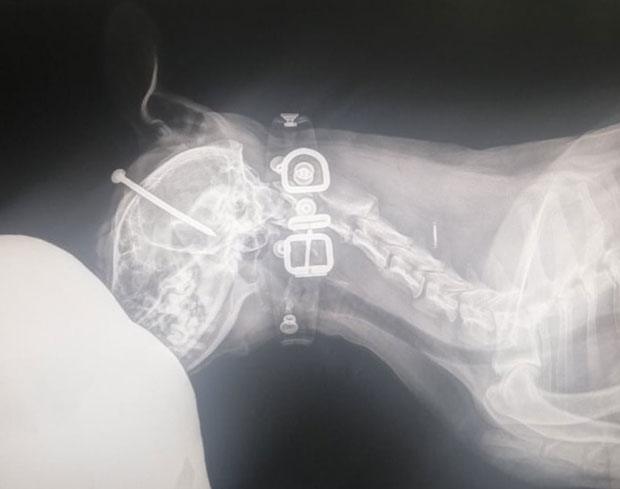

Zlostavljanje psa u Novom Sadu: DVANAESTOGODIŠNjI dečak ukucao EKSER životinji u LOBANjU!

NOVOSADSKA policija je danas pronašladvanaestogodišnjeg dečakaiz Novog Sada koji je psu zabio ekser u lobanju, saznaju “Novosti”.